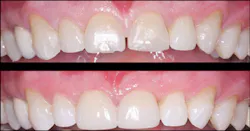

Veneers, where indicated and properly accomplished, technically have near-optimum esthetic appearance for many years (figures 5, 6). That is not the case with many PFM crowns, which often show unsightly margin exposure and loss of superficial stains after only a few years. With the popularity and increased use of lithium disilicate restorations, which do not have a metal substructure, this veneer advantage may not be as observable in the future.

Figure 5: Although these six anterior teeth had significant facial caries and discoloration and required facial and proximal reduction, they had intact lingual surfaces. Veneers instead of crowns were planned for the patient.

Figure 6: The six anterior ceramic veneers on the teeth have served the patient well for several years.